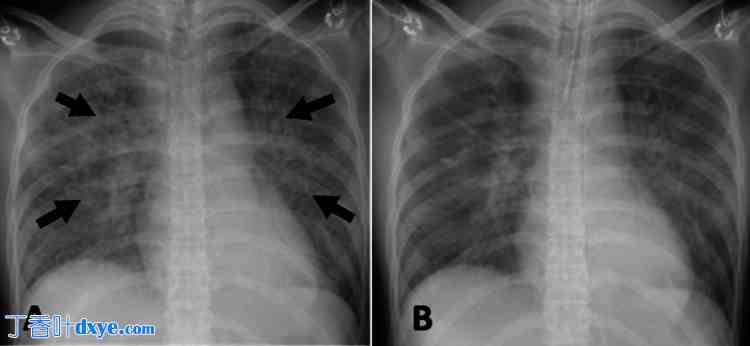

图1. 术中胸片。

(A) 气管插管前:可见肺水肿(箭头所示),可能是由于生理盐水过度吸收所致。(B) 气管插管后:应用呼气末正压通气后,肺水肿略有改善。